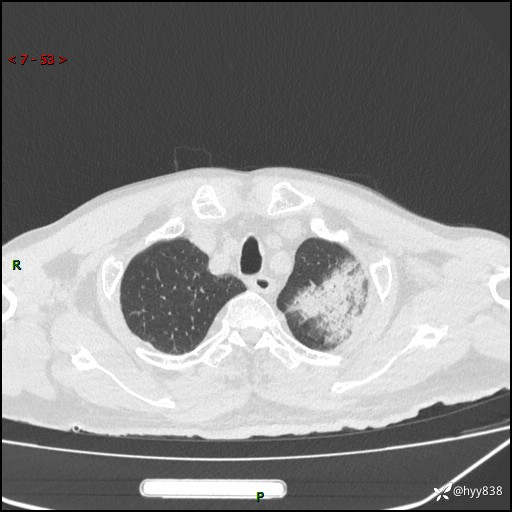

胸部CT平扫(2024.7.24)